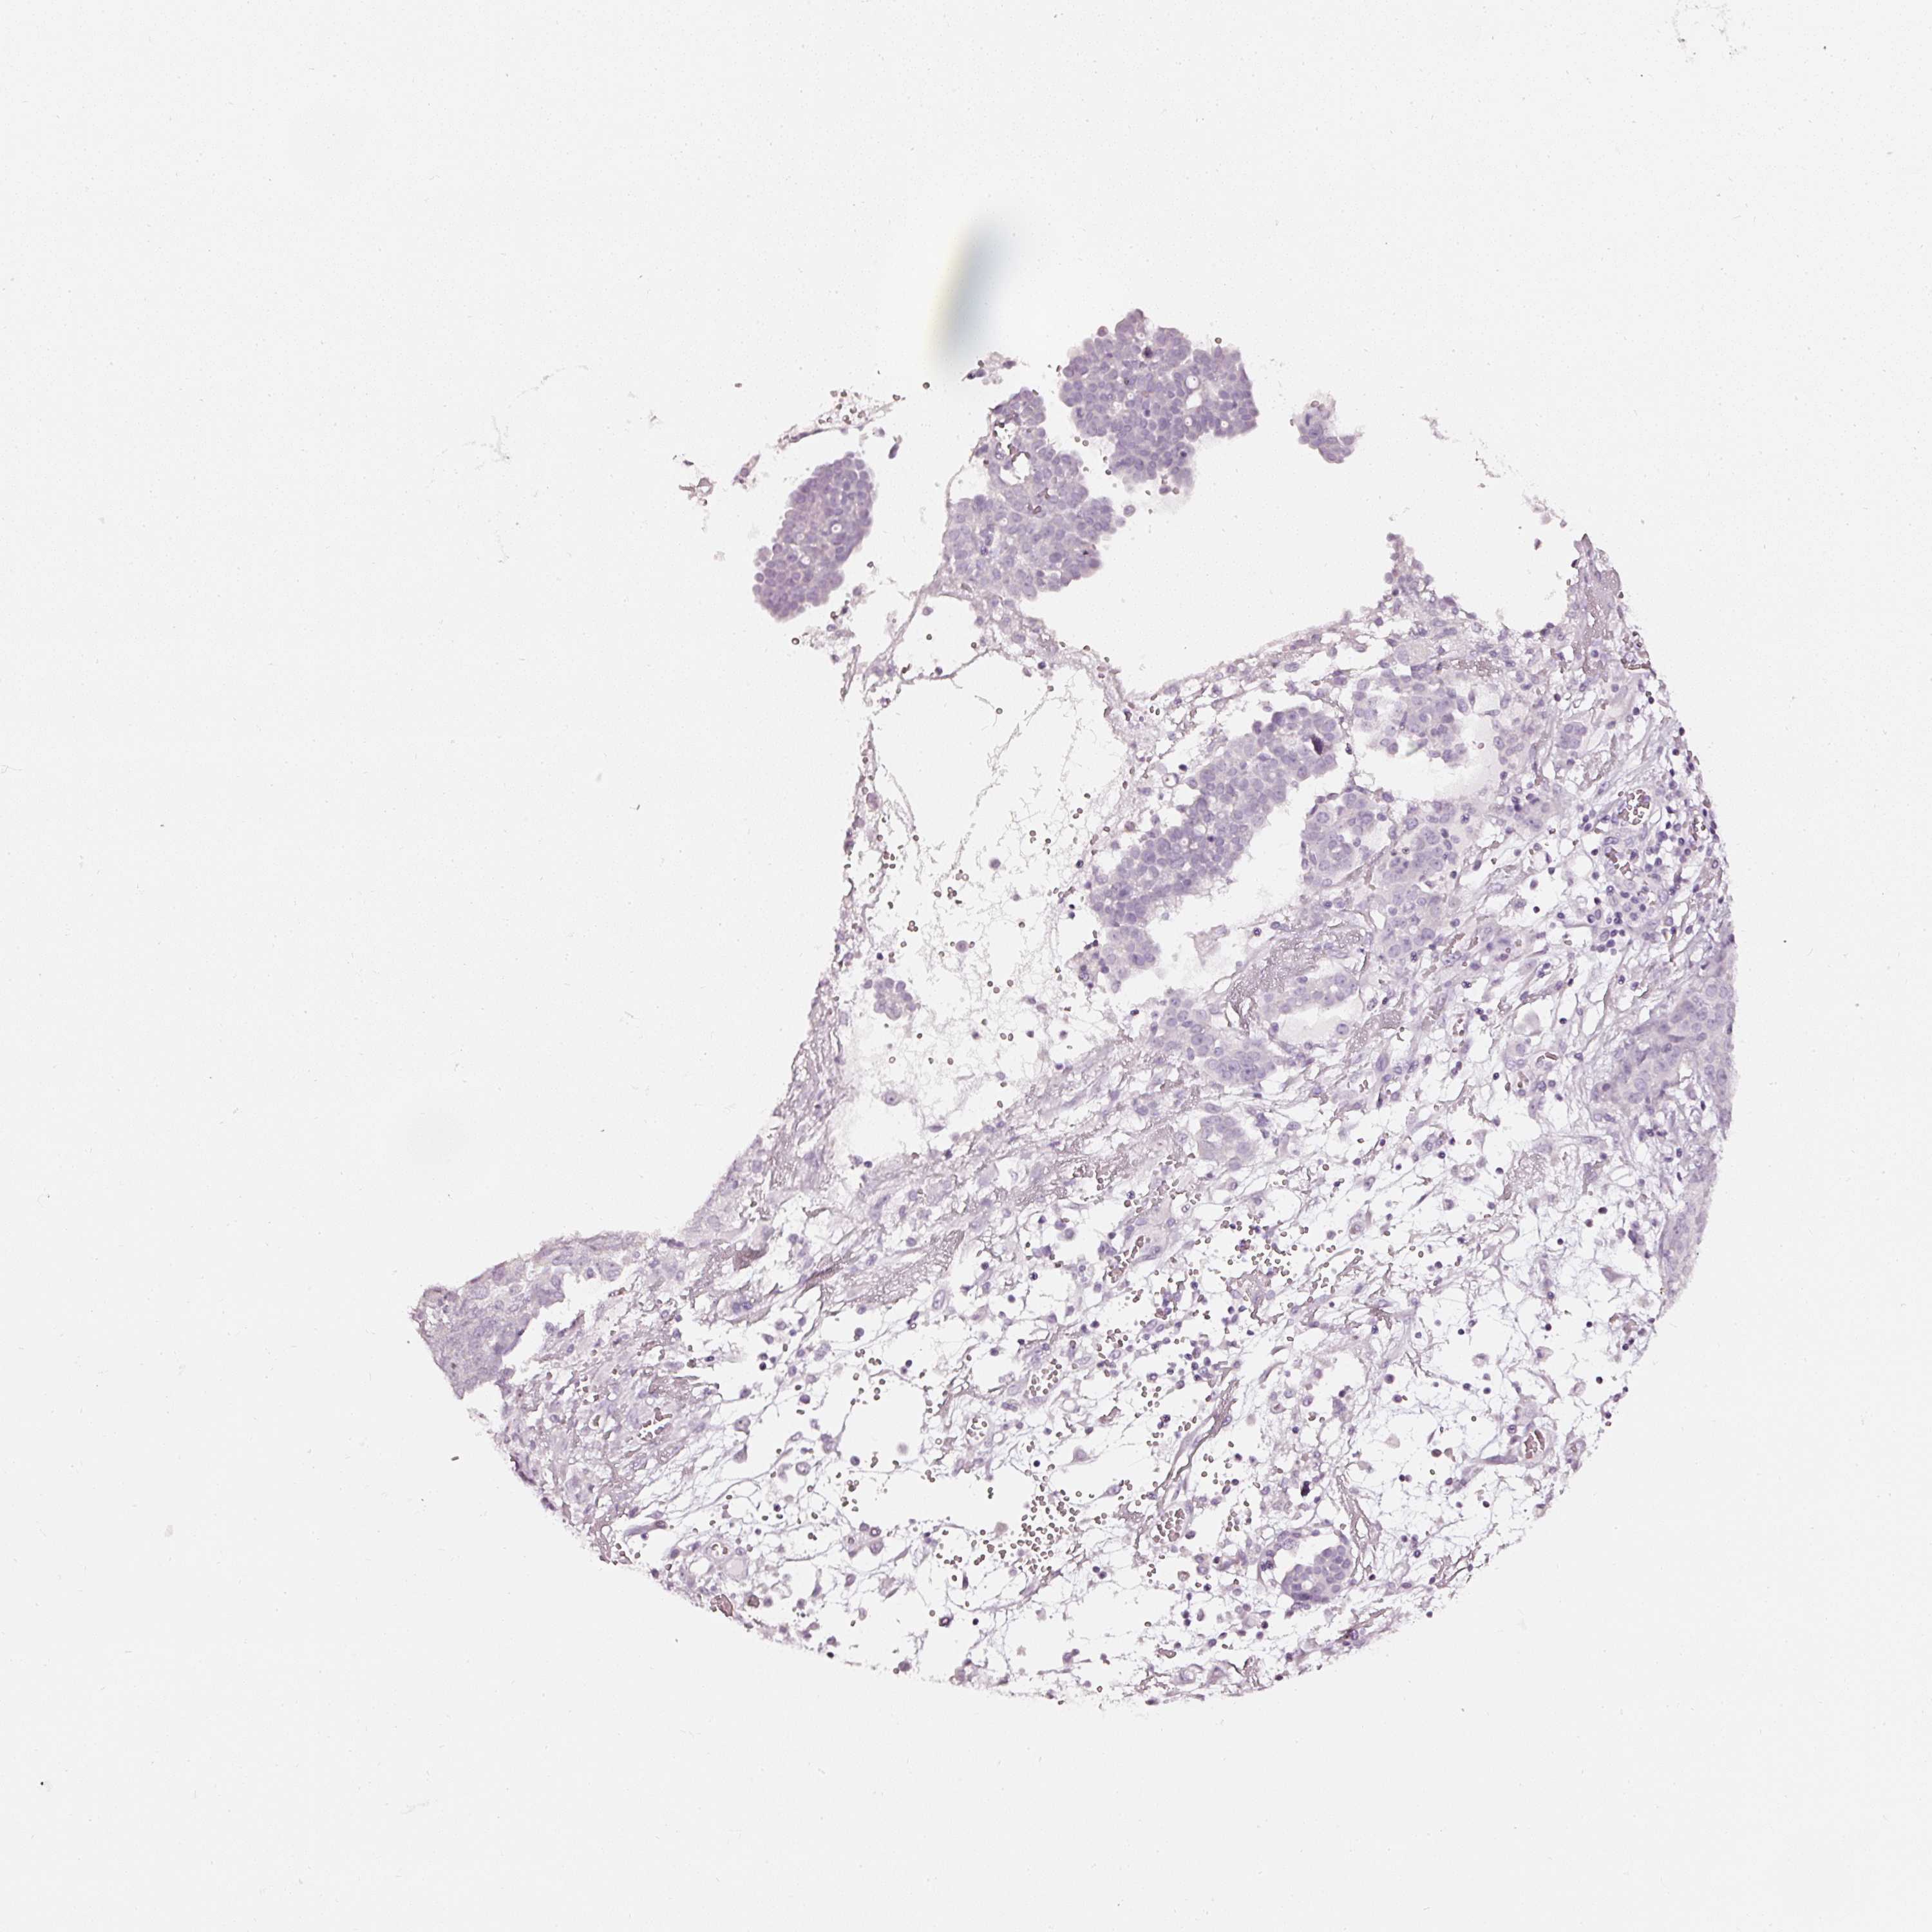

OVARIAN CANCER - Protein expressioni

A mouse-over function shows sample information and annotation data. Click on an image to view it in a full screen mode. Samples can be filtered based on level of antibody staining by selecting one or several of the following categories: high, medium, low and not detected. The assay and annotation is described here.

Note that samples used for immunohistochemistry by the Human Protein Atlas do not correspond to samples in the TCGA dataset.

Antibody stainingi

Antibody staining in the annotated cell types in the current human tissue is reported as not detected, low, medium, or high, based on conventional immunohistochemistry profiling in selected tissues. This score is based on the combination of the staining intensity and fraction of stained cells.

Each image is clickable and will lead to virtual microscopy that enables deeper exploration of all samples and also displays staining intensity scores, fraction scores and subcellular localization as well as patient and tissue information for each sample.

Carcinoma, NOS